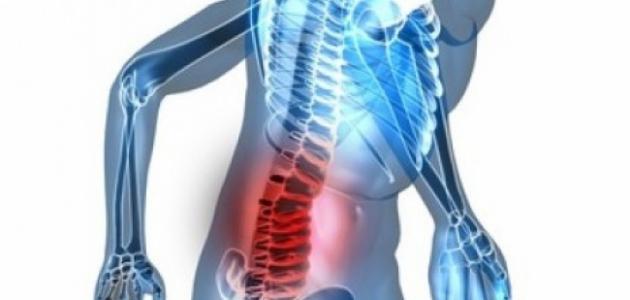

أسباب انزلاق غضروفي

هناك الكثير من الأسباب التي تقف خلف الإصابة بالانزلاق الغضروفي بالرغم من أنه يحدث أحيانا بدون أسباب، وإليك بعض الأسباب التي تؤدي إلى حدوثه.

حدوث التواء في العمود الفقري، وهذا يحدث نتيجة ضغط من نوع ما أو ربما حركة مفاجئة غير محسوبة، لذلك عليك الحرص عند التحرك بشكل مفاجئ.

ممارسة الرياضة بالأوزان الثقيلة التي تفوق قدرتك.

عدم الجلوس بشكل صحيح منتظم، فالبعض لا يعرف أن الجلوس له شكل صحي صحيح وآخر غير صحي بالمرة، ولذلك يحدث الانزلاق عندما لا تتم مراعاة ذلك.

التقدم في السن وانحناء العمود الفقري أحد عوامل الإصابة بانزلاق غضروفي.

زيادة الوزن، وهو أمر يزيد من الحمل على العمود الفقري ويأتي معه الإصابة بالانزلاق الغضروفي خاصة إذا زاد الوزن عن المُحدد بشكل مبالغ فيه.